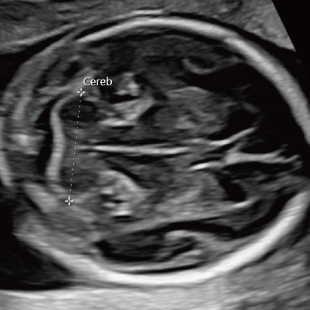

妊娠中期になると、胎児の体や内臓の構造がよりはっきりと確認できるようになります。 中期スクリーニングでは、頭部、顔面、頸部、胸部、腹部、心臓、手足、外性器、臍帯や胎盤など、全身をくまなく観察し、形態の状態を詳しく確認します。この頃に染色体数の変化を疑わせる所見が確認される事もあります。

胎児ドックの様子_中期_頭 胎児ドックの様子_中期_顔面 胎児ドックの様子_中期_心臓 胎児ドックの様子_中期_腹部 胎児ドックの様子_中期_足 胎児ドックの様子_中期_4D